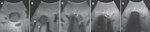

FIGURE 2

Cryoprobe Placement

Cryoablation can be performed with multiple applicators, allowing the operator to sculpt a cryolesion for maximum tumor coverage with minimum collateral damage. Until recently, cryoablation was associated with large-diameter applicators (3 to 8 mm), but small-gauge devices (down to 17-gauge) are now available for percutaneous use (Figure 2). Regardless of the approach to the patient-open, laparoscopic, or percutaneous-one of the main advantages of cryoablation over the heat-based ablation methods is the ability to visualize the developing iceball with ultrasound, computed tomography, and magnetic resonance imaging (Figure 3), and the excellent correlation between the location of the iceball and the zone of cell death.[7-9] This is an important advantage of cryoablation, as the success of any ablation technique is dependent on the ability to visualize the complete destruction of the targeted tumor.